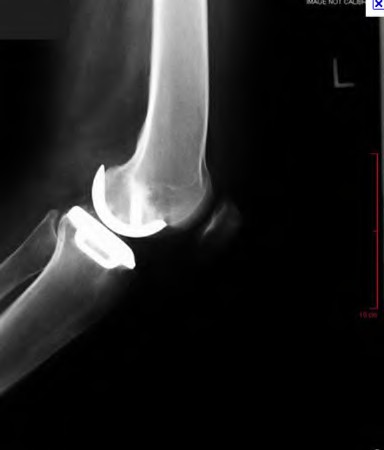

A 60-year-old male tennis player undergoes a unicompartmental knee arthroplasty (UKA) shown in Figures A and B. Which of the following statements regarding this procedure is true?

Figures A and B depict radiographs of a unicompartmental knee arthroplasty (UKA). UKA kinematics have been shown to most closely approximate native knee kinematics.

In an in vitro cadaver study, Patil et al found that TKA significantly changed knee kinematics while the unicompartmental replacement preserved normal knee kinematics.

Fisher et al performed a retrospective study comparing the short-term outcomes of small-incision unicompartmental knee arthroplasty (UKA) with standard total knee arthroplasty (TKA) in 91 consecutive patients older than 70 years. They found: 1) Blood loss was significantly more for the TKA group, as was the need for blood transfusion. 2) Patients with unicompartmental replacements had a much quicker return of function and discontinuation of pain medication. 3) While knee scores and ROM were similar preoperatively, both were better in the unicompartmental group at each postoperative time interval. 4) Narcotic use and length of hospital stay were also significantly less for the unicompartmental group. Therefore answers 2,3,4 and 5 are false.